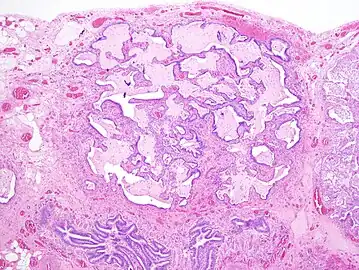

Appearance of usual interstitial pneumonia (UIP) in a surgical lung biopsy at low magnification. The tissue is stained with hematoxylin (purple dye) and eosin (pink dye) to make it visible. The pink areas in this picture represent lung fibrosis (collagen stains pink). Note the "patchwork" (quilt-like) pattern of the fibrosis.

Appearance of honeycomb change in a surgical lung biopsy at low magnification. The dilated spaces seen here are filled with mucin. Hematoxylin-eosin stain, low magnification.